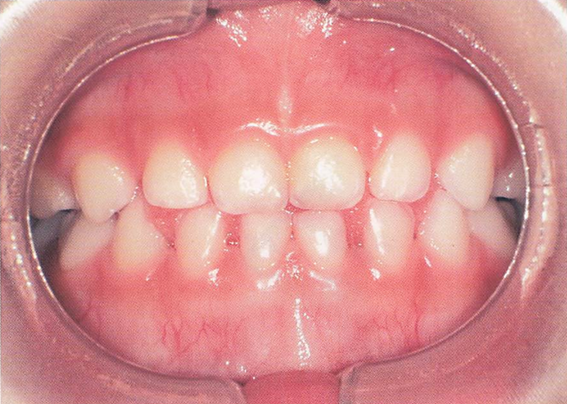

午前-56

6歳の男児。母親とともに定期歯科健康診査のため来院した。口腔内診査の結果、永久歯への生え代わりはなく、下顎前歯部の歯間部に空隙が認められた。 口腔内写真を別に示す。 この空隙はどれか。1つ選べ。

a.顎間空隙

b.鼓形空隙

c.発育空隙

d.霊長空隙

解答を見る

c